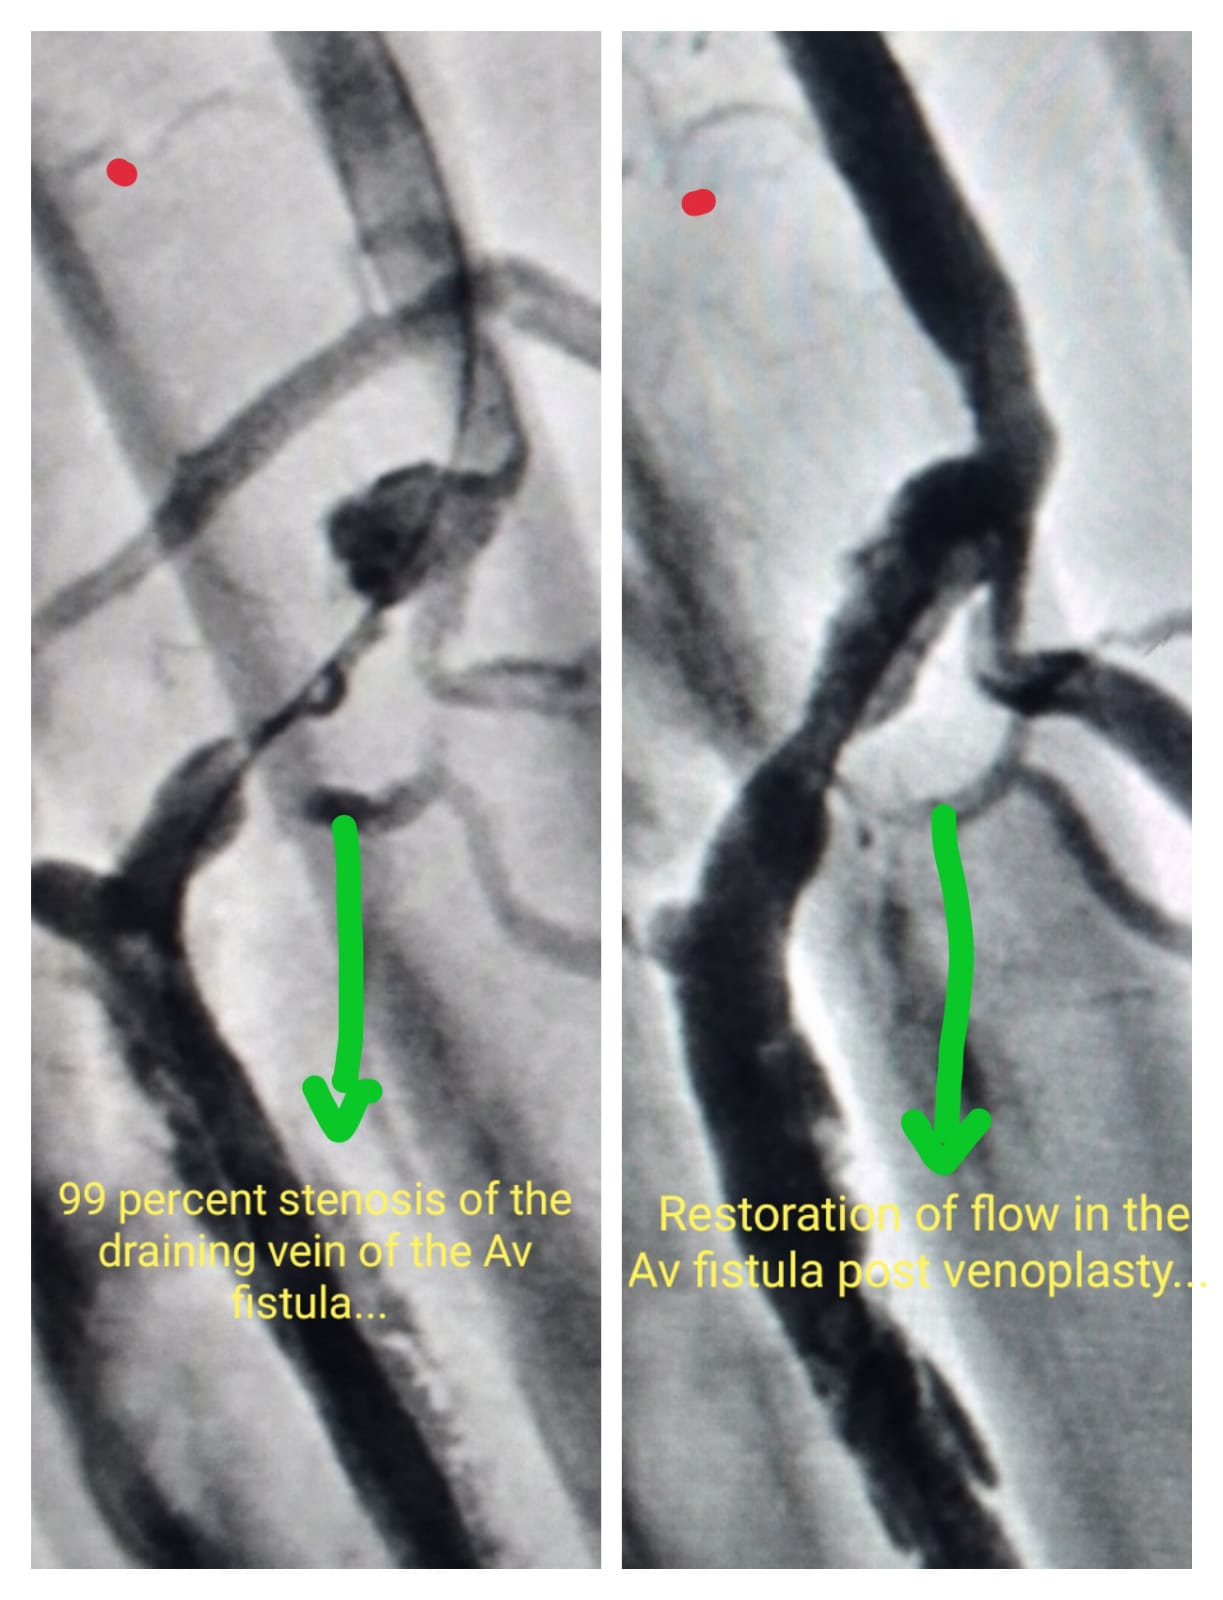

Dialysis AV Fistula procedure - Pre Procedure & Post Procedure